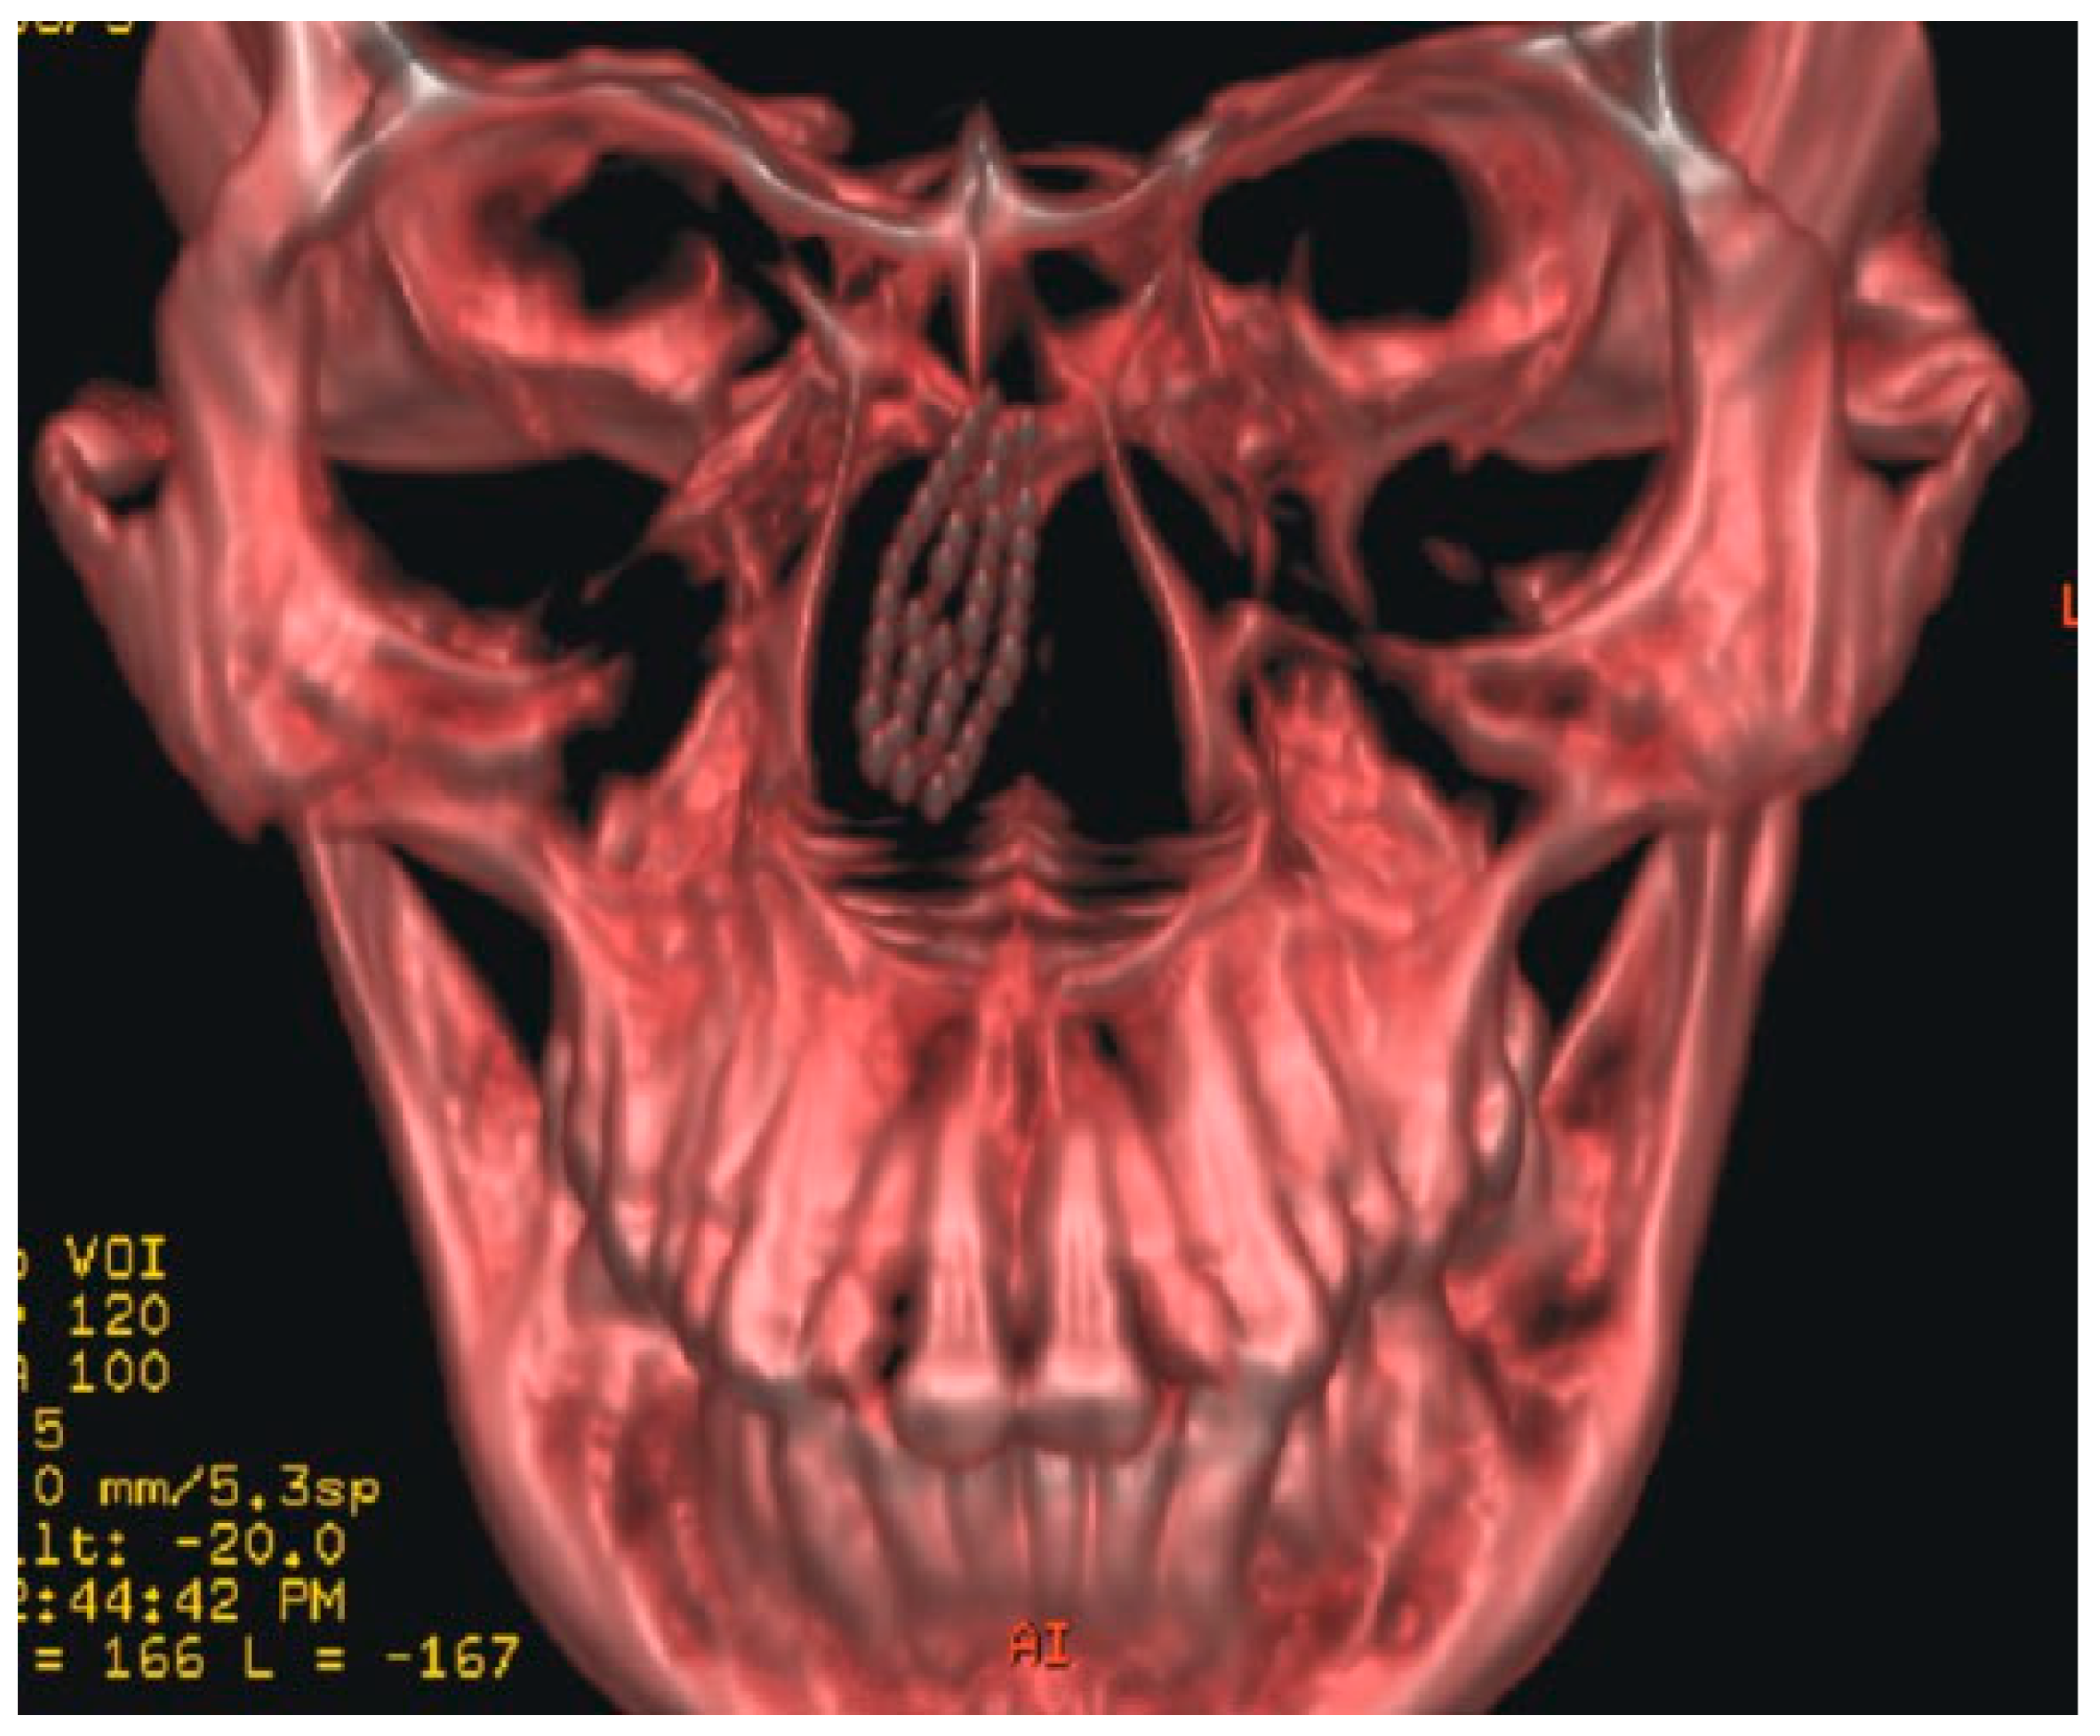

A 42-year-old woman reported to the Department of Oral and Maxillofacial Surgery with a toothbrush head lost in her nose. On careful elicitation of related events, we discovered that she had reportedly placed the tooth-brush into her nose to relieve herself of the irritable itching she was experiencing in her nose. She suffered from allergic rhinitis since childhood and frequently experienced nasal itching especially in the early morning hours. In this instance, she slipped on a wet floor and the resultant fall caused the tooth brush to snap into two pieces leaving the brush head inside the nose. The accident caused profuse nasal bleeding, which was controlled by the patient with finger pressure using a handkerchief. A computed tomographic (CT) evaluation was undertaken at a radiodiagnosis center (Figure 1) on the recommendation of a primary health care facility she had visited initially. An attempt was made at the primary health center to retrieve the brush head with a curved hemostat, which proved unsuccessful and led to a further episode of epistaxis. She was then referred to our center. She was brought to our department 3 hours after the accident. Visual inspection of the nasal cavity revealed right-sided vestibulitis with clotted blood in the right nasal cavity. The toothbrush head could not be seen on visual inspection with a nasal speculum and headlamp. Visual inspection of the pharynx was unremarkable. The patient did not complain of right nasal obstruction. The patient confirmed that she had not swallowed any portion of the object. The CT showed the presence of the toothbrush head in the superior right nasal cavity at the junction between the lateral and medial nasal walls. The brush head had caused a deviation of the nasal septum to the left (Figure 2). The patient was prepared for nasal endoscopy. The right nasal cavity was sprayed with a local anesthetic aerosol agent (lidocaine USP 15%, ICPA Health Products Ltd., Mumbai, India) and phenylephrine 0.25% applied on a cotton pellet. After 5 minutes, an endoscope was introduced into the right nasal cavity and showed a large wound in the upper part of the nasal cavity with clotted blood on the surface. No object could be identified in the nasal cavity. The patient was prepared for surgery under regional anesthesia. The patient was placed in a supine position with the head elevated ~20 degrees. The forehead, nose, and face were prepared with an antiseptic solution (2% cetavlon followed by alcohol). The nasal cavities were packed loosely with 1-cm ribbon gauze soaked in 4% lignocaine for 15 minutes. Anesthesia of the external nose was achieved using bilateral infraorbital nerve blocks (lignocaine 2% with 1:200,000 adrenaline, Xicaine, ICPA Health Products Ltd., Mumbai, India) with additional infiltrations at the base of the columella, the dorsum of the nose, the infratrochlear nerve, and the external nasal nerves, and about 0.5 mL of the solution was injected into the membranous septum. An open rhinoplasty approach with a transcolumellar extension was used. A marginal incision along the caudal border of the lateral crura of the lower lateral cartilages was made and carried medially and inferiorly along the cephalic border of the medial crus up to its lower part and then extended with a right angle turn to the caudal margin of the medial crus. A combination of sharp and blunt dissection was used to expose the entire nasal skeleton up to the nasal bones. The object was found to be lodged between the upper-right lateral cartilage and the nasal septum, with its bristles embedded into the right-upper lateral cartilage and the nasal septum (Figure 3). Dissection of the object from between the upper lateral cartilage and the nasal septum was performed after incising the upper-right lateral cartilage submucosally from the nasal cartilage and then proceeding with the exposure of the nasal septal cartilage. The object was delivered in one piece (Figure 4). Hemostasis was achieved with the use of electrocautery where indicated. Closure of the wound was achieved with polyglycolic acid 910 for the nasal mucosa and the nasal cartilages. Skin closure was achieved with prolene sutures. Bilateral nasal packs were placed. No intraoperative or postoperative complications were witnessed, and the patient was discharged on the third postoperative day.

Figure 2. Three-dimensional reconstruction of computed tomography images showing position of the foreign body.